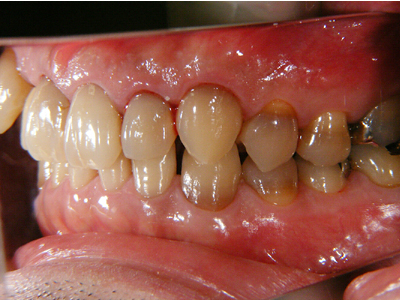

この患者様の主訴は右下7番(第2大臼歯)の詰め物の脱離でした。口腔内写真を撮らせていただくと右上の八重歯(3番の唇側転移)が顕著でその叢生の結果、周囲が不潔となり歯肉炎およ2番(第2前歯)の歯頚部の異常他退縮が認められます。

5. 初診時右側

八重歯を中心とした叢生が顕著です。その周囲のみが既にクラウンとなっており、不適合が目立ちます。